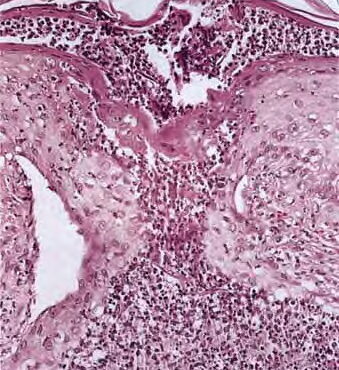

Read MoreForeign body reaction = ارتكاس للجسم الاجنبي Foreign Body Reactions Foreign substances, when injected or implanted accidentally into the skin, can produce a nonallergic foreign-body reaction or, in persons specifically sensitized to them, an allergic response (. In addition, certain substances formed within the body may produce a nonallergic foreign-body reaction when deposited in the […]